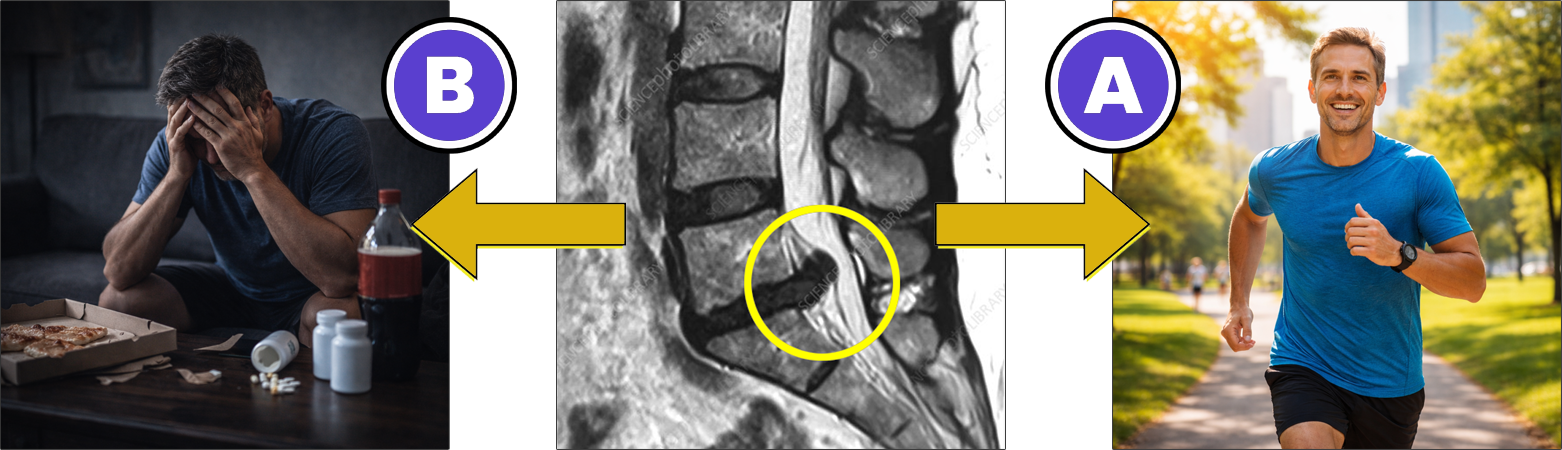

En cuadros crónicos, lo que explica el dolor es siempre lo que sale en la resonancia magnética o los estudios de imagen (hernias, protrusiones, estrechamiento del canal, listesis, cambios facetarios, escoliosis, etc.).

Lo que muestra la evidencia científica es muy distinto. Si bien los resultados de una resonancia pueden aportar información, en la gran mayoría de los casos (+ 90%) no explican ni justifican las causas reales por las cuales muchas personas sienten y experimentan un dolor que no desaparece

Que para resolver de forma final y definitiva tu cuadro de dolor no tenés que enfocarte únicamente en las "lesiones" o patologías mecánicas que salieron en tus estudios de imagen.